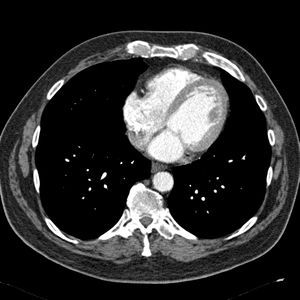

MRA Image Immediately Post-ablation LGE-MRI Image CT Image

Carma reg CT.jpg

• CT scans are less common but can be acquired with a contrast agent to delineate the bounds of the blood pool. Many of our CT scans are acquired with a C-arm fluoroscopy unit rather than a traditional CT scanner.

CT to LGE-MRI

• Shape-analysis studies -- Image processing group

CT better captures the shape of the LA and is more easily segmented. We hope to compare the volumes and shapes of CT-derived LA segmentations to those of MRI-segmented images. We will need to register the CT and MRI images to make this work. A potential challenge here is the scarcity of CT scans (namely normal CT scans, although, DynaCT scans are also not commonly acquired).